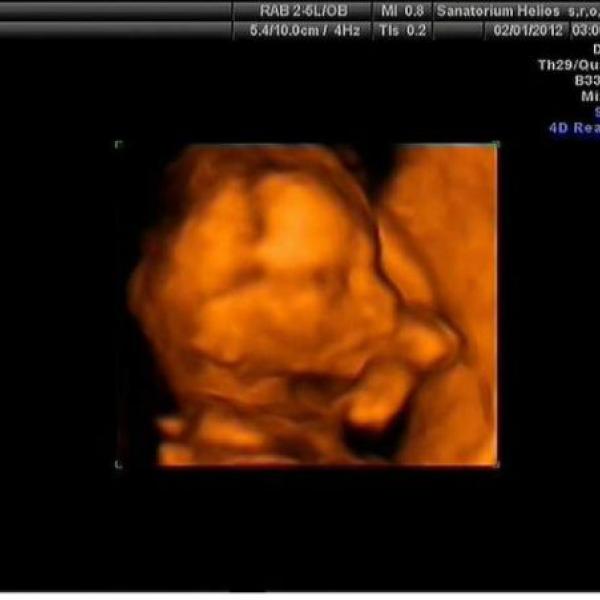

Ahojky holkyyyyyy,

tak dnes máme za sebou 3D ultrazvuk a paráda, hezky jsme si prcka prohlídli a máme 5 foteček za 200Kč, co víc si přát :)